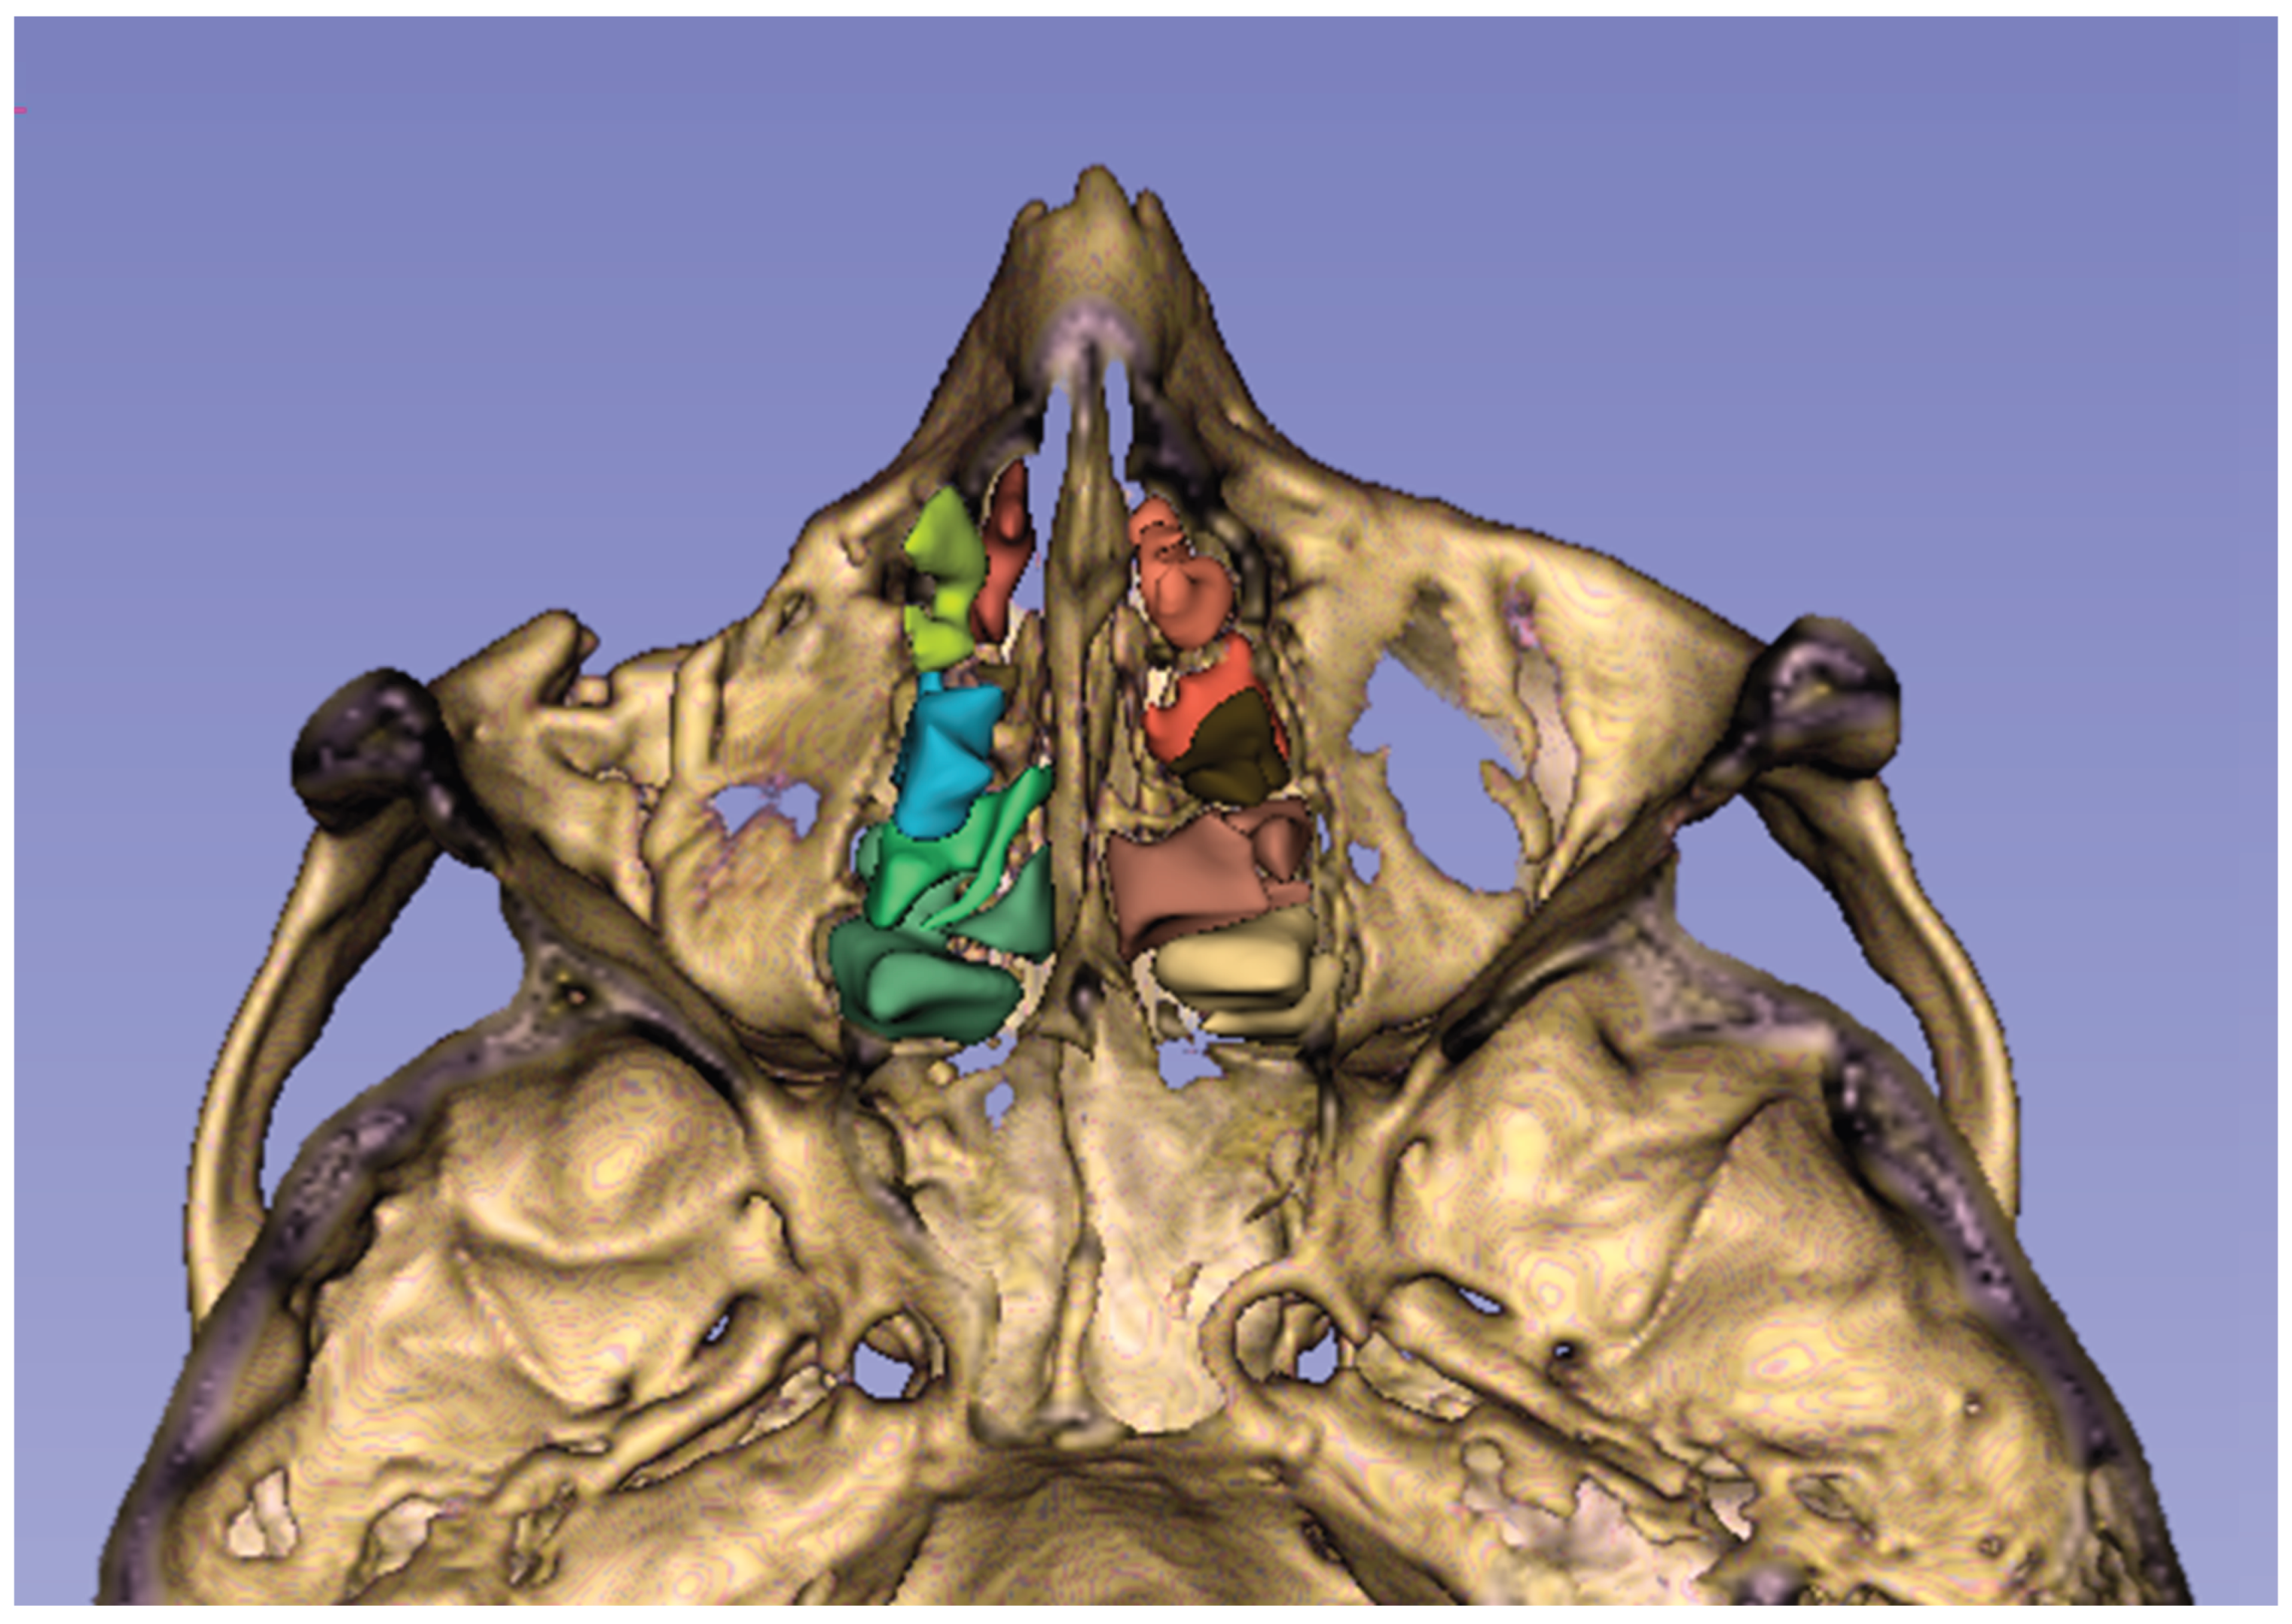

Figure 1. Axial view of the maxillofacial skeleton through the ethmoid sinus, with the ethmoid air cells colored. The figure was obtained by the 3D Slicer application.

The ethmoid sinus is a unique structure in that it contains multiple air chambers, unlike the other paranasal sinuses, which usually consist of a single air compartment. This special air space, located between the nasal and oral cavities, consists of multiple air cells formed by thin bones and separated from each other by the basal lamella of the middle turbinate [6] (Figure 1). Removal of ethmoidal septa during endoscopic sinus surgery has been shown to cause a change in the biomechanics of the orbit, leading to an increased risk of OBF, which is more pronounced in the medial wall than in the orbital floor [7,8]. We hypothesized that in a large ethmoid sinus, aligning the air cell walls relatively farther apart would reduce their buttressing effect for the orbital walls. The purpose of this study was to investigate whether increased ESV constitutes a risk factor for the occurrence of OBF following craniofacial trauma. Besides, we aimed to explore whether there is a relationship between ESV and OBF patterns.